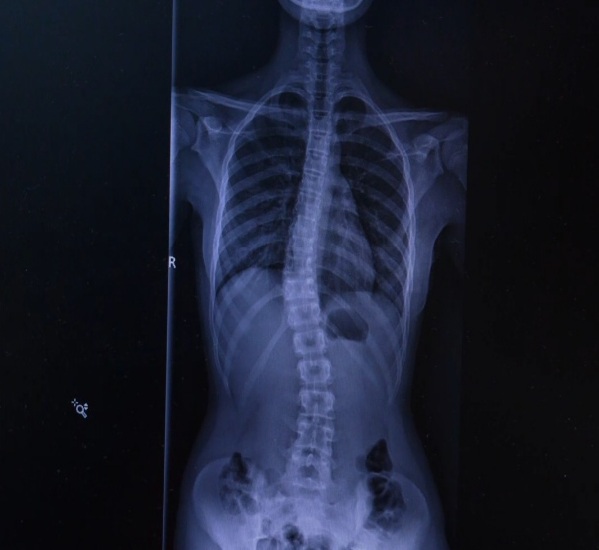

Tak to určil u nás ortopéd z rtg. Niečo o krku rozprával , že nevie či korzet , ale že máme sa objednať do Šnopu. A intenzívne dovtedy cvičiť. Rehabilitačná zas tvrdí, že to až 28 stupňov nie je tak uvidíme.

Predtým mal 15 a zrazu o 9 mesiacov 28, ale to bolo v októbri.

Náš ortopéd to určuje z rtg iba vyšetril ho v predklone zbežne ani botasky si nemusel vyzuť.

@kacena4 aj u nás na základe rtg odmeral, inak nič nerobil predklon spravil.